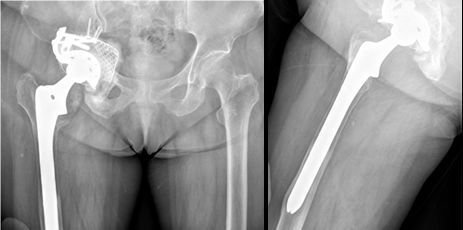

图1 各种原因所致人工髋关节翻修

图4 76岁,女性患者,9年前于外院行全髋关节置换术,术后恢复良好;2年前开始出现疼痛,近半年无法行走,需轮椅代步。

图5 翻修术后髋关节假体稳定,假体位置角度良好,可早期下地活动锻炼